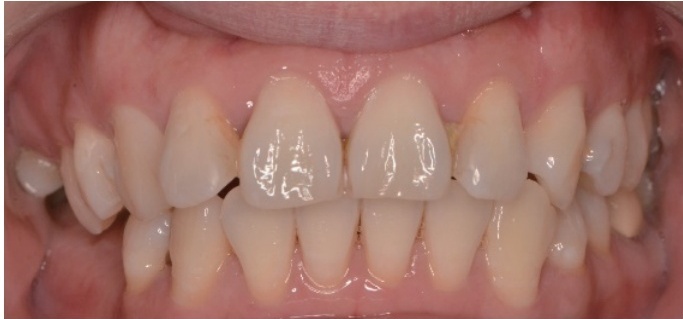

牙龈糜烂:相同症状是同一疾病三个案例,还是三种不同疾病?

病史摘要:本文介绍3位牙龈糜烂患者。患者1为52岁女性,多牙牙龈红肿、糜烂半年,伴双颊白纹,有高血压、糖尿病史。患者2为35岁女性,上前牙牙龈肿痛5个月余,外院治疗未好转。患者3为37岁女性,右下牙龈溃疡、肿痛2个月,外院诊断“牙周炎”治疗无效且病情加重。三位患者均否认乙肝、结核等传染病史、外伤史、手术史、输血史、药物及食物过敏史,无吸烟、酗酒、冶游史,也无相关疾病家族史。 诊疗过